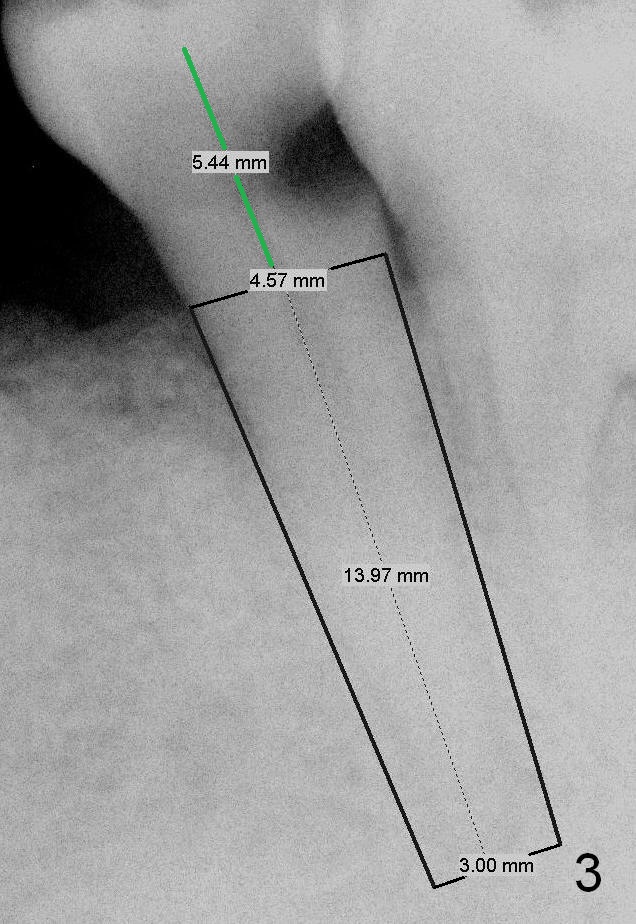

A 56-year-old man has poor dentition (Fig.1). The tooth #20 fractures (not shown) after root canal therapy (Fig.2). A 4.5x14 mm bone-level implant is planned (Fig.3).

The 2nd drill will be 2.5 mm reamer (17 mm from the gingival margin). To placed the implant, use a latch driver, followed by latch adapt and torque wrench. If insertion torque is high (>45 Ncm), place cemented abutment (probably 5824 (Fig.3 green line (5.44 mm)) and fabricate an immediate provisional.